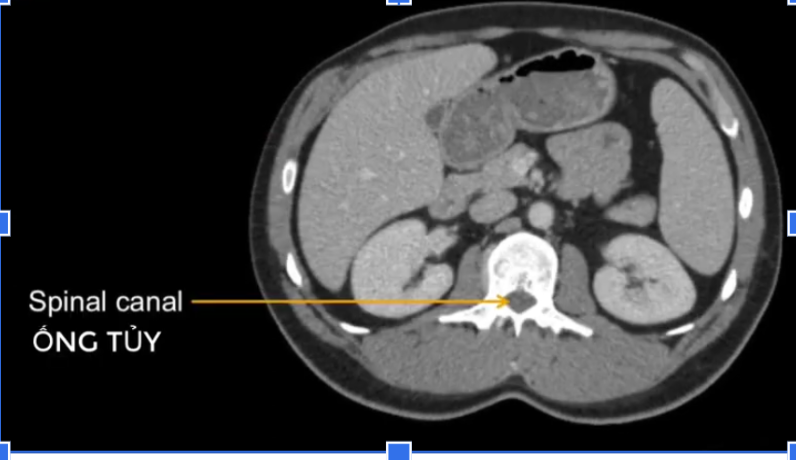

TM gan ở đâu? TM chủ dưới ? ĐM chủ?